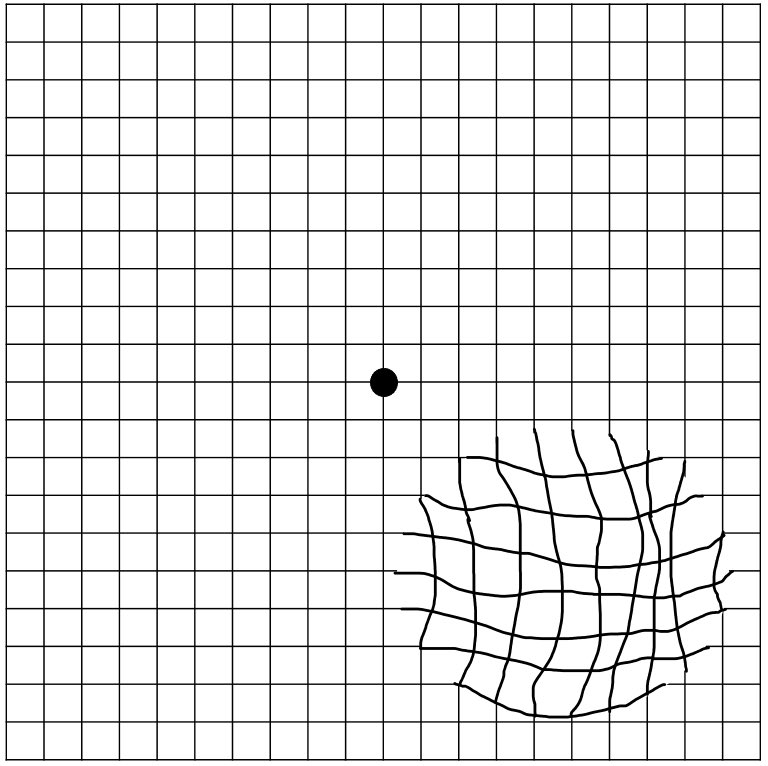

تموّج (تعرجات) في الرؤية (في حال حدوث مضاعفات مثل الاوعية الدموية في الشبكية)